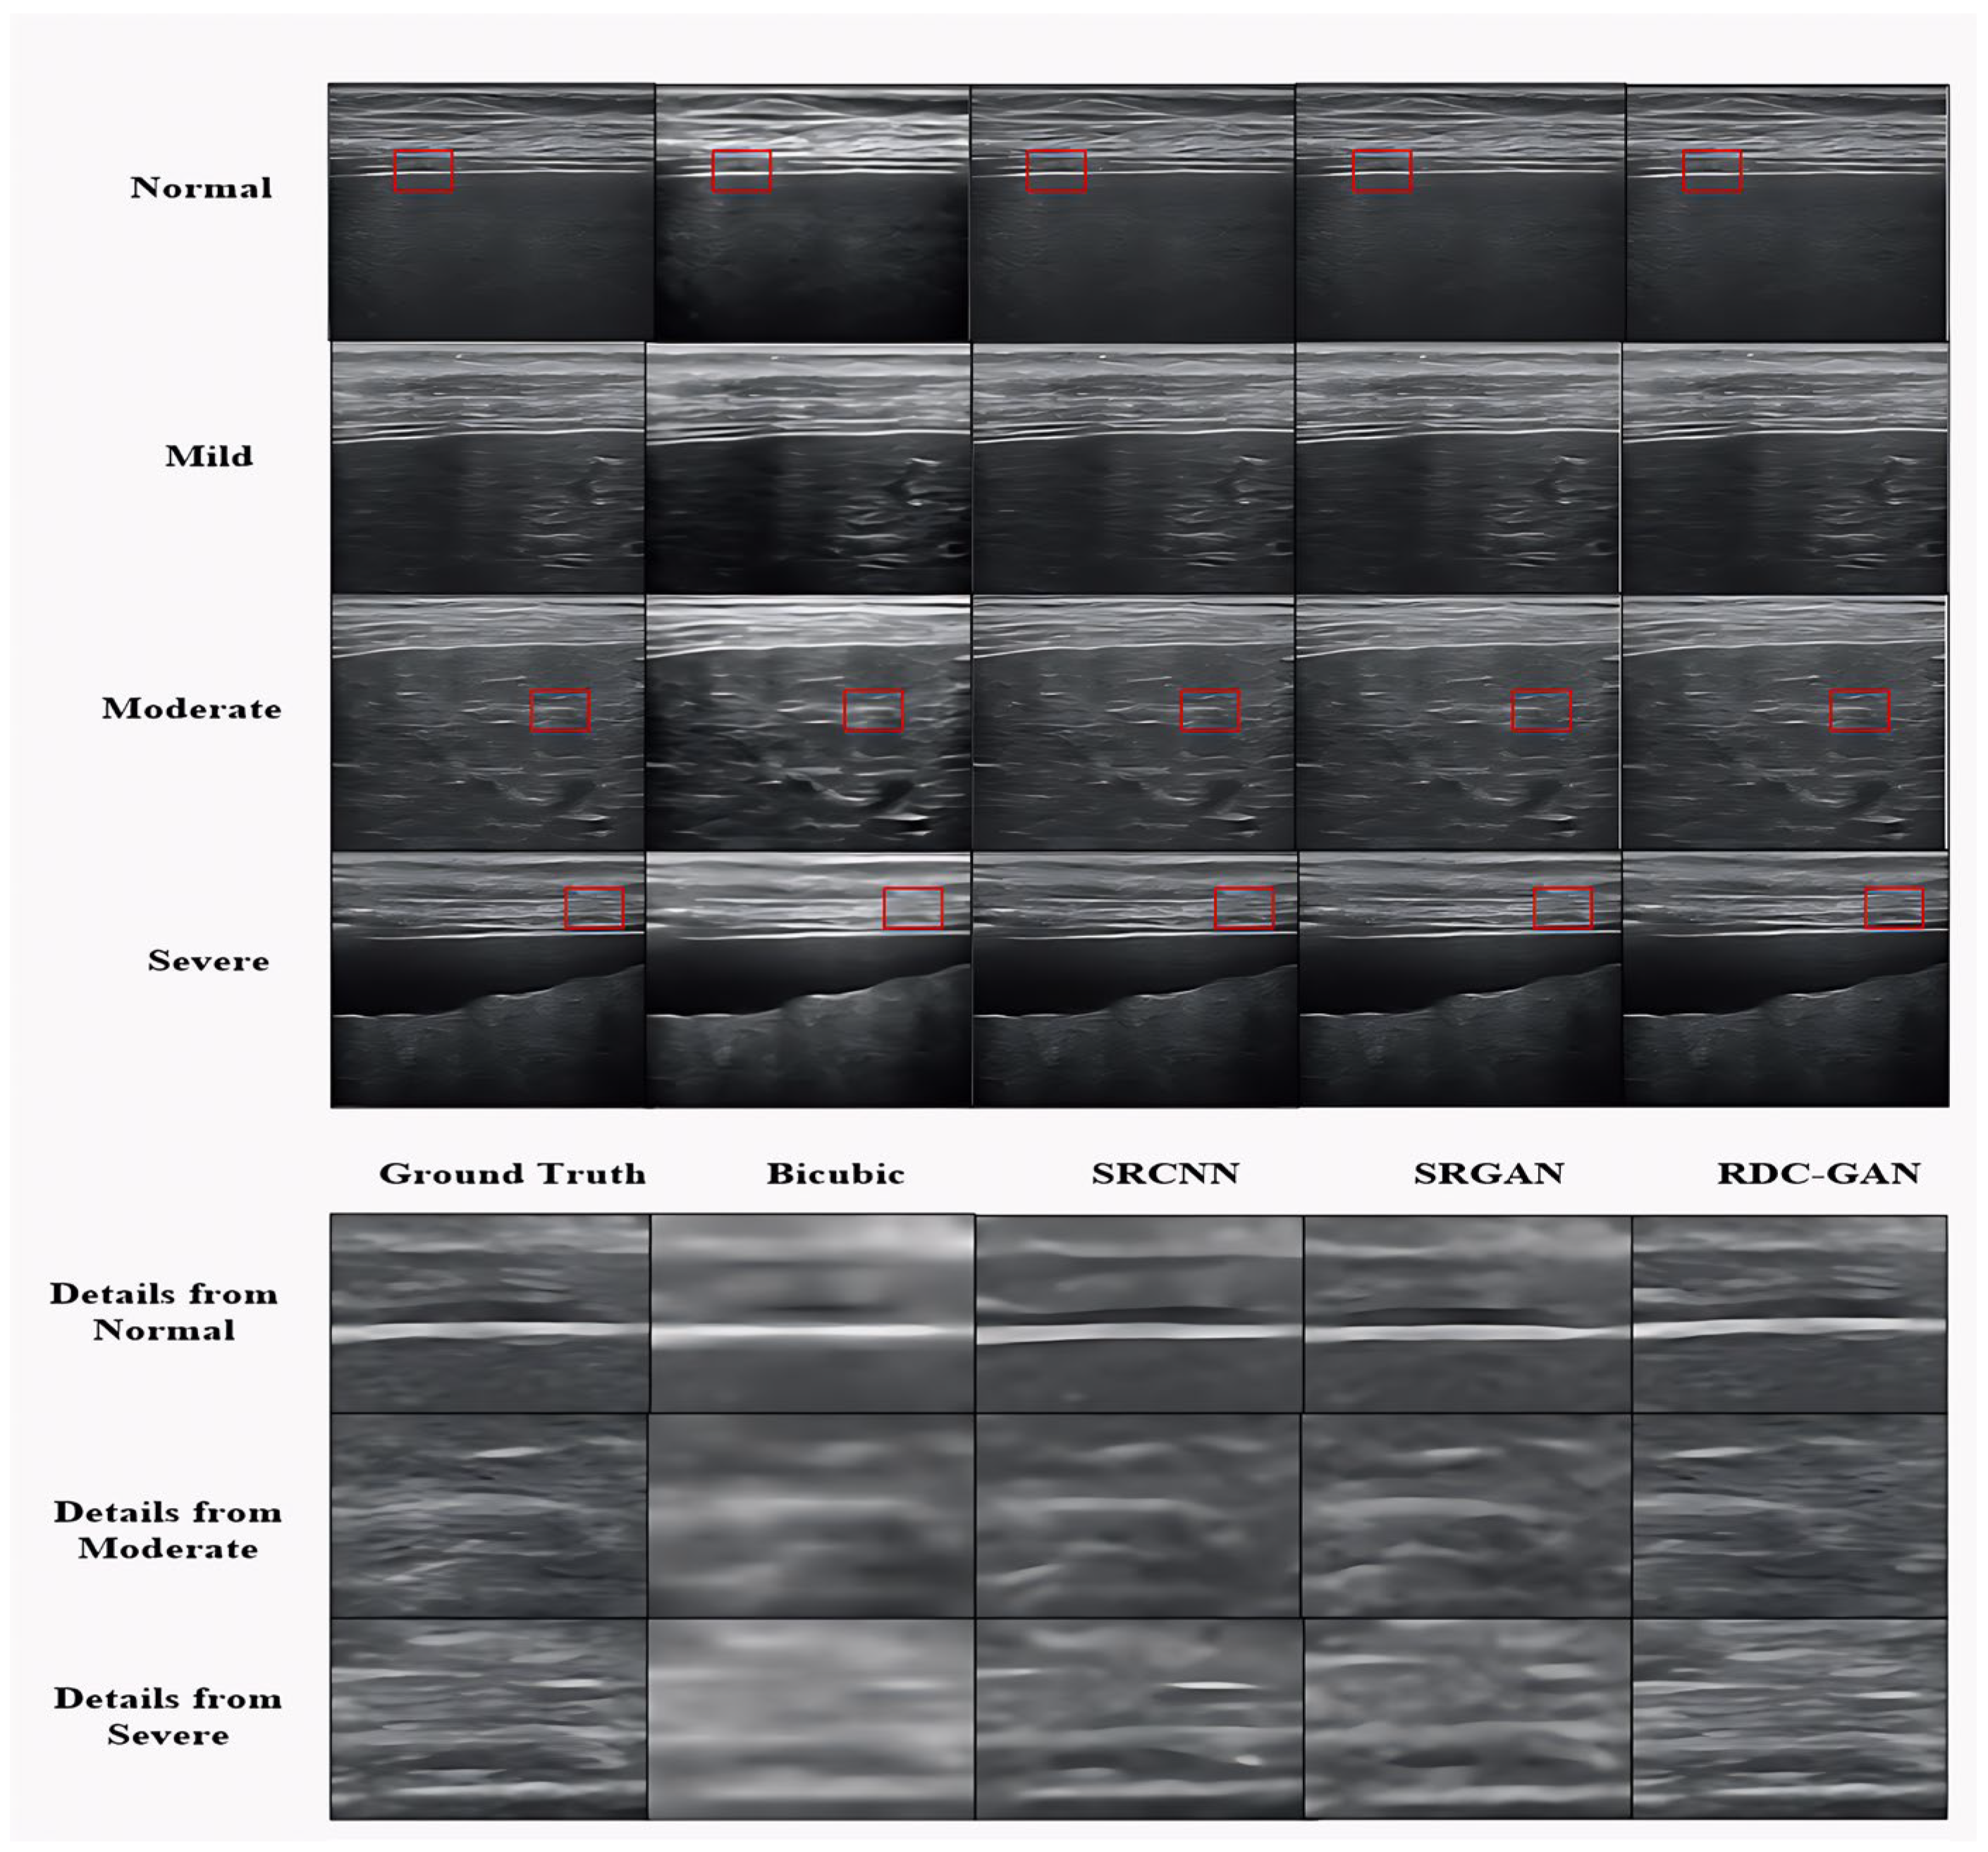

4.2. Qualitative Analysis

| Stage | Algorithm | PSNR (dB) | SSIM (0–1) |

|---|---|---|---|

| Normal | Bicubic | 20.82 ± 0.07 | 0.74 ± 0.003 |

| SRCNN | 30.20 ± 0.08 | 0.85 ± 0.005 | |

| SRGAN | 24.97 ± 0.09 | 0.60 ± 0.004 | |

| RDC-GAN | 32.51 ± 0.07 | 0.89 ± 0.002 | |

| Mild | Bicubic | 24.31 ± 0.08 | 0.77 ± 0.003 |

| SRCNN | 31.30 ± 0.06 | 0.86 ± 0.005 | |

| SRGAN | 28.63 ± 0.05 | 0.78 ± 0.005 | |

| RDC-GAN | 32.21 ± 0.08 | 0.87 ± 0.003 | |

| Moderate | Bicubic | 21.61 ± 0.09 | 0.70 ± 0.004 |

| SRCNN | 29.48 ± 0.07 | 0.78 ± 0.002 | |

| SRGAN | 25.10 ± 0.06 | 0.59 ± 0.003 | |

| RDC-GAN | 32.04 ± 0.07 | 0.87 ± 0.003 | |

| Severe | Bicubic | 20.52 ± 0.05 | 0.79 ± 0.004 |

| SRCNN | 30.16 ± 0.06 | 0.85 ± 0.005 | |

| SRGAN | 23.95 ± 0.09 | 0.63 ± 0.003 | |

| RDC-GAN | 33.44 ± 0.06 | 0.87 ± 0.003 |